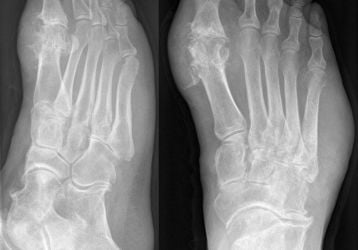

Разрыв связок голеностопа: степени, причины, симптомы, методы лечения травмы

Лечение разрыва связок голеностопного сустава. Степени разрыва, причины, симптомы и диагностика. Народные средства лечения, профилактика травмы.